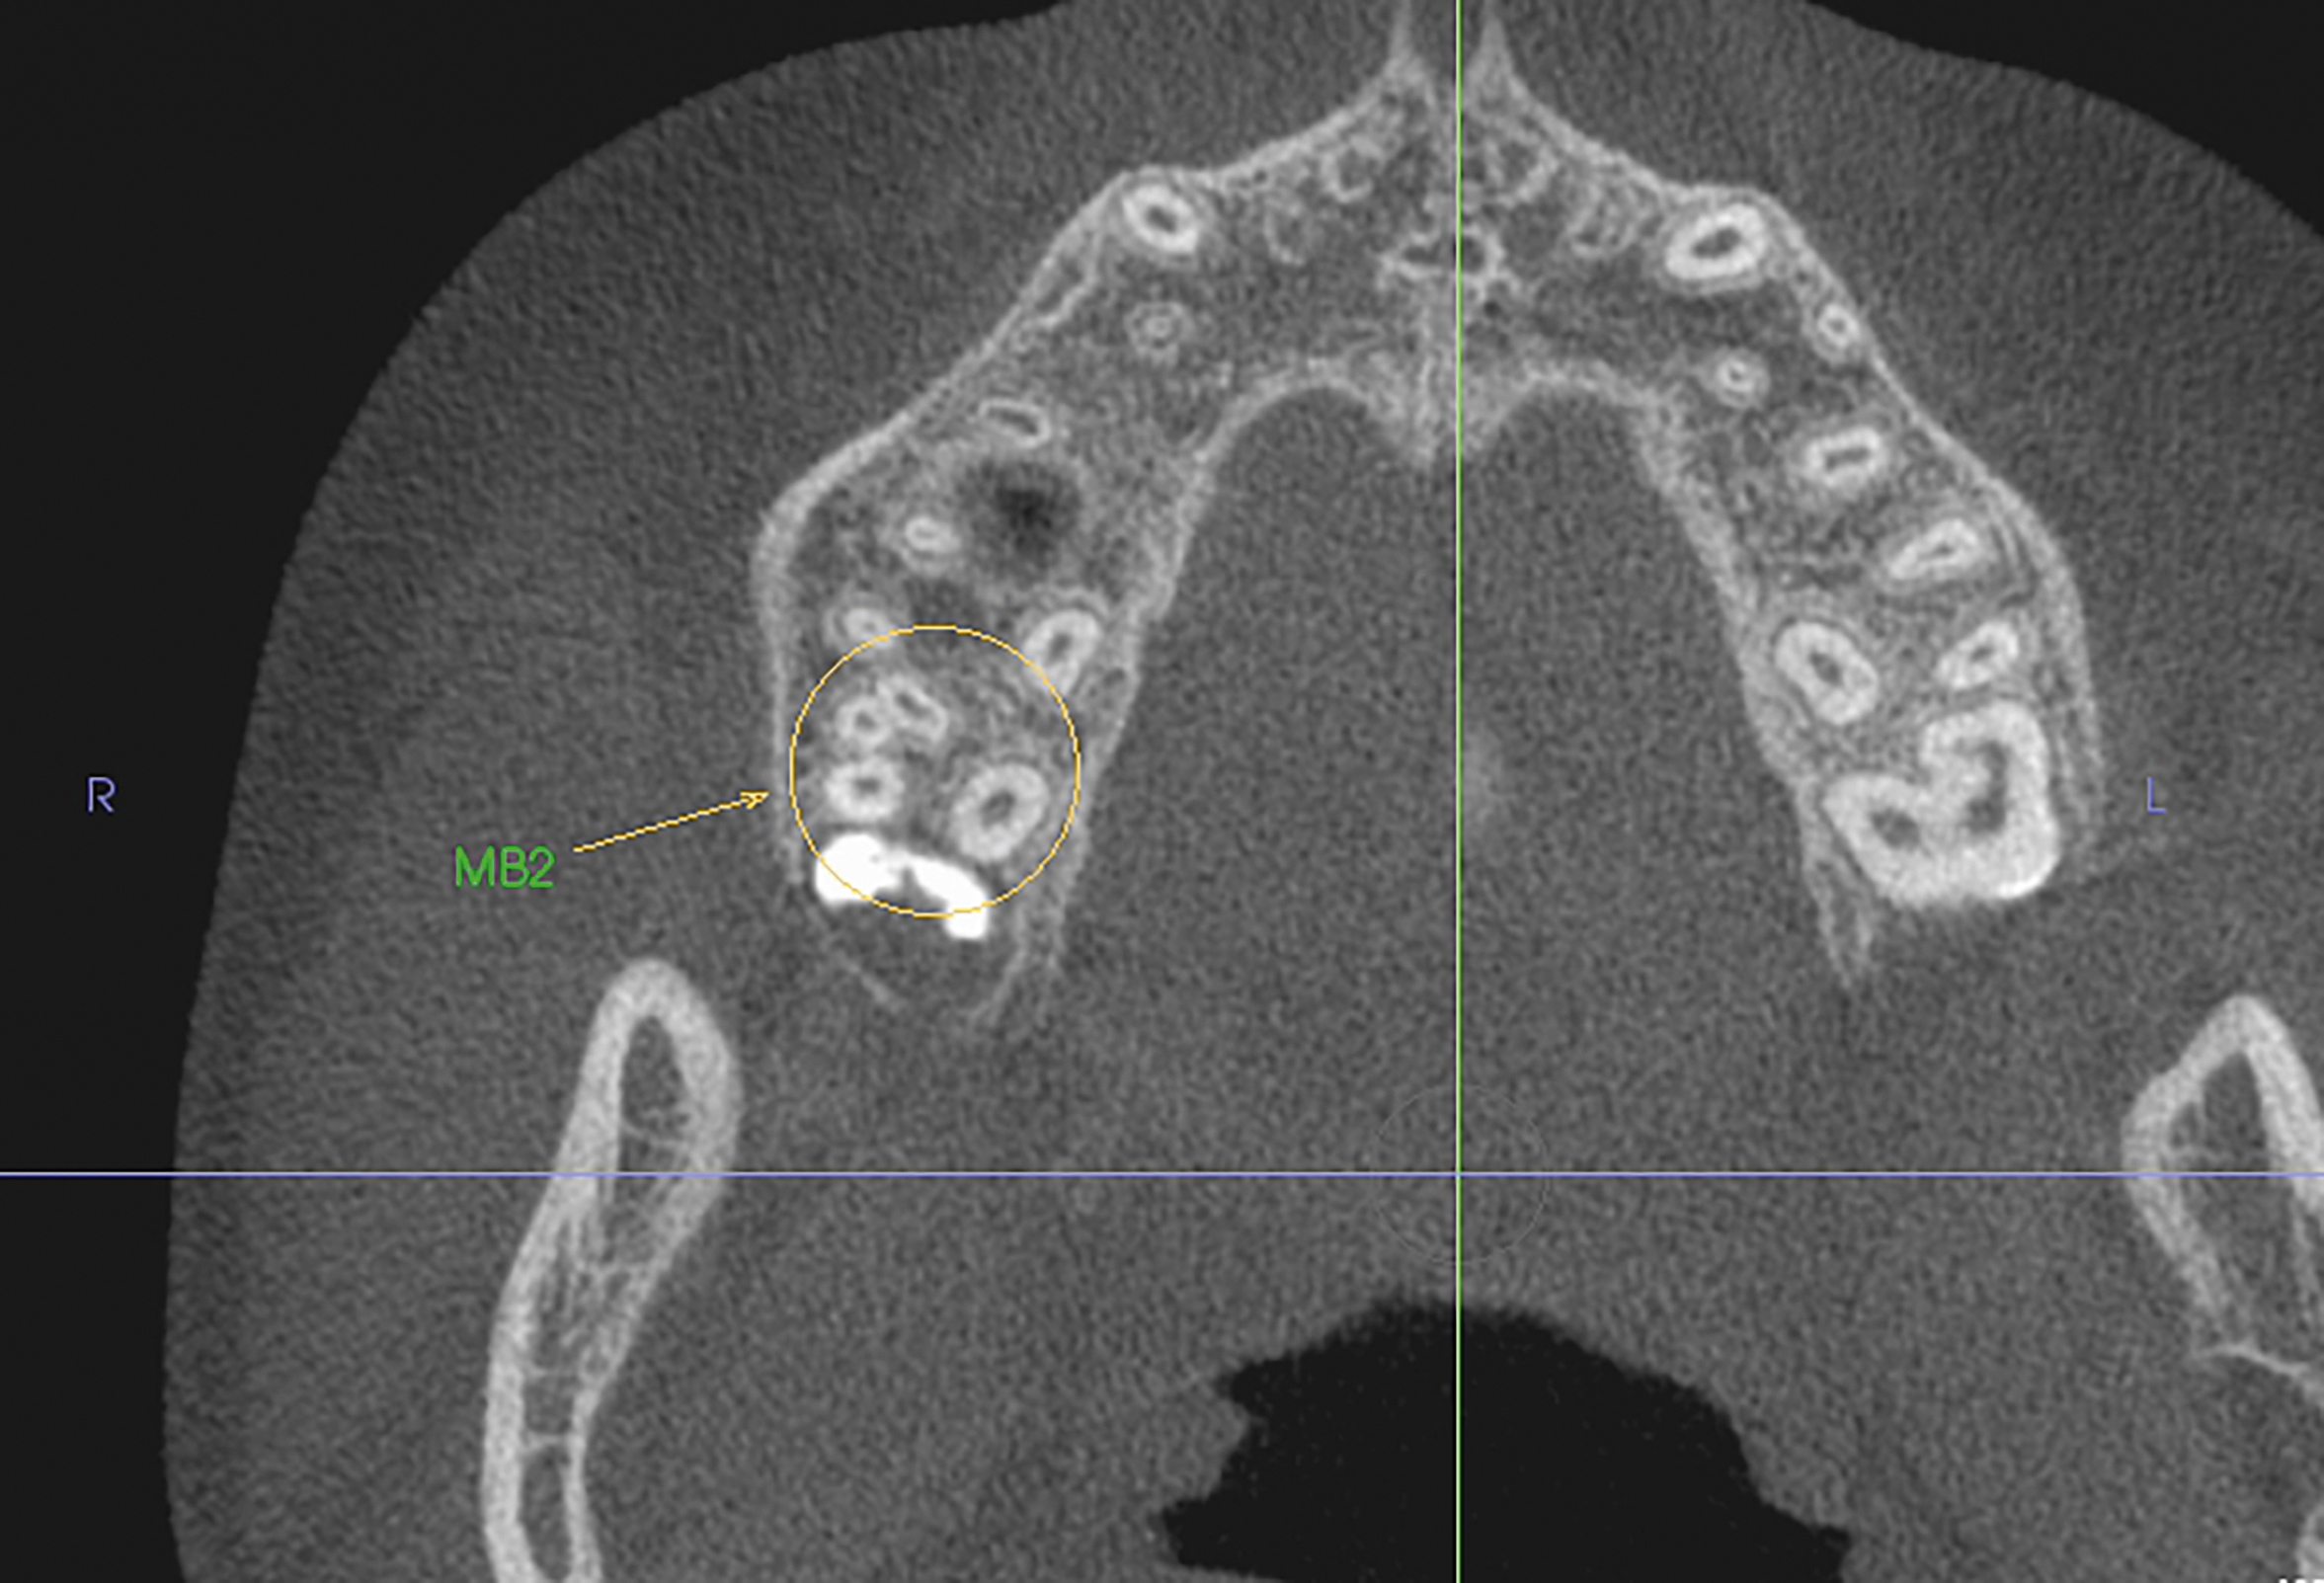

当院には正確で安全な治療を行うための検査機器をとして、最新鋭の歯科用CTシステムを導入しております。このシステムは、低い被ばく線量(総合病院などの医科用CTの1/10以下)で、3次元データの情報を得ることができ、これまでのレントゲン検査の診断が難しかった部分の診断も行えます。これにより患者さんのへのわかりやすい説明と更なる治療成績の向上が見込めます。